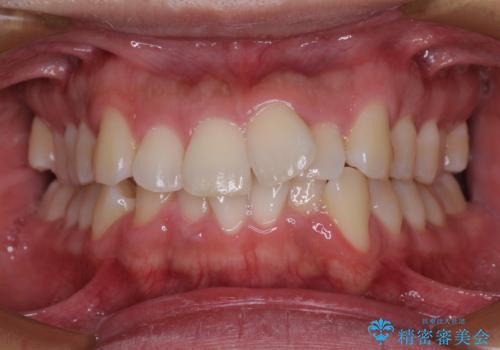

部分矯正を併用した奥歯のインプラント補綴治療

部分矯正期間中はアンカースクリューやフック、ゴムなどが粘膜にあたり、大変な思いをすることになりましたが、そのおかげでインプラント補綴した歯と最後方歯の位置が非常に良好となり、まるでご自身の歯のように咬むことができるようになりました。